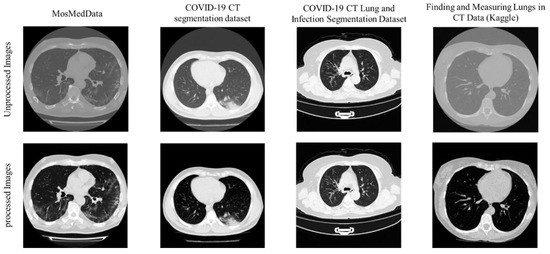

2.2. Pre-Processing

| Dataset Name | Task | # of Patients | # Images Used | Lung Mask | Lesion Mask |

|---|---|---|---|---|---|

| COVID-19 CT Lung and Infection Segmentation Dataset | Lung segmentation, lesion segmentation, and COVID-19 detection | COVID-19: 20 | 3520 | ✔ | ✔ |

| COVID-19 CT segmentation dataset | Lung segmentation | COVID-19: 9 | 829 | ✔ | |

| Finding and Measuring Lungs in CT Data (Kaggle) | Lung segmentation | Not available | 267 | ✔ | |

| MosMedData * | External Validation | 1110 | 46,411 | ✔ |